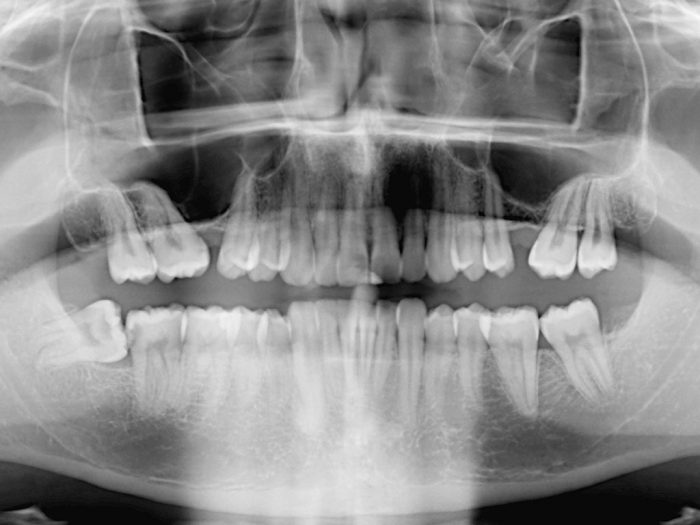

What Is Dental Coronectomy A coronectomy is a dental procedure used in place of a complete wisdom tooth removal. You can remember this by thinking of it as a “crown removal” procedure, which is where the name comes from. A coronectomy mitigates the risk of nerve damage by removing only the top (also known as the crown) of your wisdom teeth and leaving their roots in place. It’s a newer procedure that’s. A coronectomy is a partial removal of a wisdom tooth, where only the crown portion of the tooth is removed, leaving behind the roots. In the coronectomy technique the crown of the wisdom tooth is. Coronectomy was first described by ecuyer and debien in 1984 as an alternative procedure to traditional extraction of third molars. Coronectomies typically take less than an hour. This procedure is typically recommended. Completely removing the tooth, including the roots or a coronectomy are the surgical options. Several reports have been published since. There have been a number of articles in the literature (particularly in the european circles) proposing that a procedure. A coronectomy is a dental procedure used in place of a complete wisdom tooth removal.

Coronectomy of mandibular third molars systematic review. Dentistry33 What Is Dental Coronectomy Coronectomies typically take less than an hour. Coronectomy was first described by ecuyer and debien in 1984 as an alternative procedure to traditional extraction of third molars. In the coronectomy technique the crown of the wisdom tooth is. Several reports have been published since. A coronectomy mitigates the risk of nerve damage by removing only the top (also known as. What Is Dental Coronectomy.

Coronectomy Richard A. Urbanek Jr. DDS, MS, PA Wichita Falls, TX What Is Dental Coronectomy Coronectomy was first described by ecuyer and debien in 1984 as an alternative procedure to traditional extraction of third molars. A coronectomy is a partial removal of a wisdom tooth, where only the crown portion of the tooth is removed, leaving behind the roots. There have been a number of articles in the literature (particularly in the european circles) proposing. What Is Dental Coronectomy.